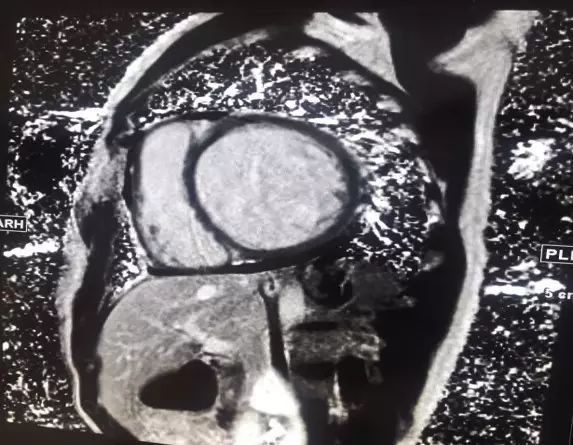

MRI

►左室腔明显扩大,室间隔及左室壁普遍变薄,各节段运动减弱

►心肌延迟强化未见明显异常

►考虑符合扩心病、心衰